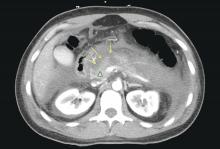

Infected pancreatic necrosis: Solid arrows indicate air within the peri-pancreatic collection.